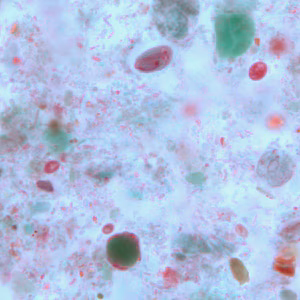

A five-year-old child went to a local clinic with complaints of abdominal cramping, excessive gas, diarrhea, and weight loss. Stool specimens were collected in formalin and polyvinyl alcohol (PVA) and sent to the local public health laboratory for routine ova-and-parasite (O&P) examination. Figures A–D show what was observed on a trichrome-stained slide prepared from stool preserved in PVA. All images were taken at 1000x magnification. What is your diagnosis? Based on what criteria?

Figure A